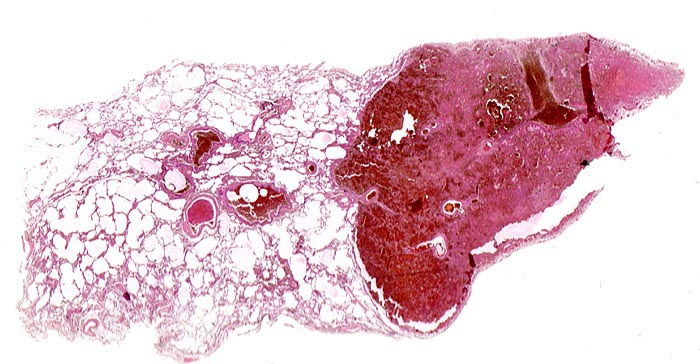

PathoPic – image database / PathoPic ID 3887 - hämorrhagischer Lungeninfarkt

hämorrhagischer Lungeninfarkt

Frische blutdurchtränkte dreieckige Nekrosezone ohne Organisationszeichen in der Peripherie des Infarktes. Als Ursache für den Infarkt lässt sich im angrenzenden Lungenparenchym ein frischer Embolus in einem peripheren Lungenarterienast nachweisen. Auch dieser zeigt keine Organisationszeichen (kein Kontakt zwischen Gefässwand und Embolus).

Tiefe Beinvenenthrombosen bei metastasierendem Prostatakarzinom. Koronare Herzkrankheit.